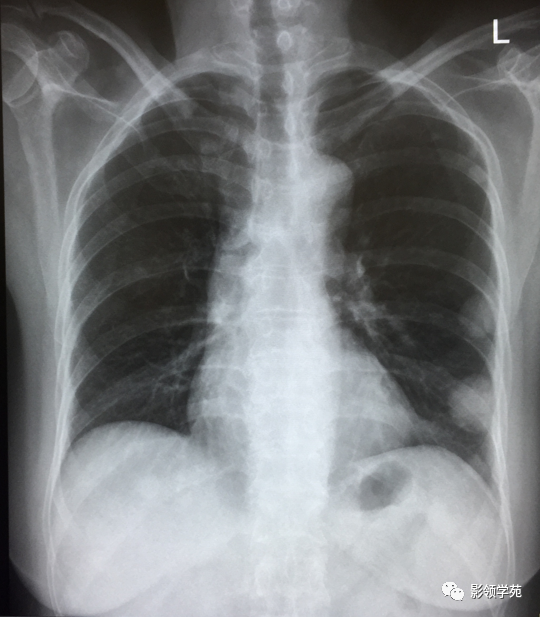

淋巴转移:肺门影增大,自肺门向外部规则索条状影(下图)

双肺淋巴道转移癌。胸部正位片示双侧中下肺野多发结节状及网格状高密度结节影,可见克氏B线(下图)